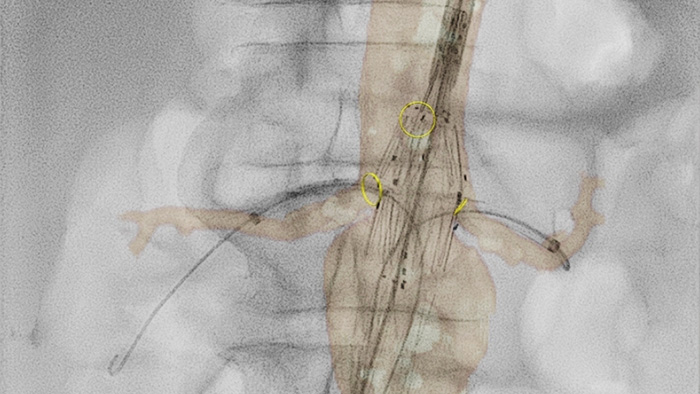

VesselNavigator proporciona una hoja de ruta 3D, intuitiva y continua, basada en conjuntos de datos de la angiografía por tomografía computarizada (ATC) y la angiografía por resonancia magnética (ARM) existentes para guiarlo a través de la vasculatura durante los procedimientos aórticos. En un estudio se demostró un promedio de 170 ml de reducción del contraste durante la reparación endovascular de aneurismas aórticos complejos con el uso de la guía de fusión de imágenes de la ATC de VesselNavigator.1 En otro estudio se mostró una reducción en el tiempo promedio del procedimiento de 6,3 a 5,2 (1,1) horas durante la FEVAR/BEVAR con la guía de fusión de imágenes de la ATC de VesselNavigator.2